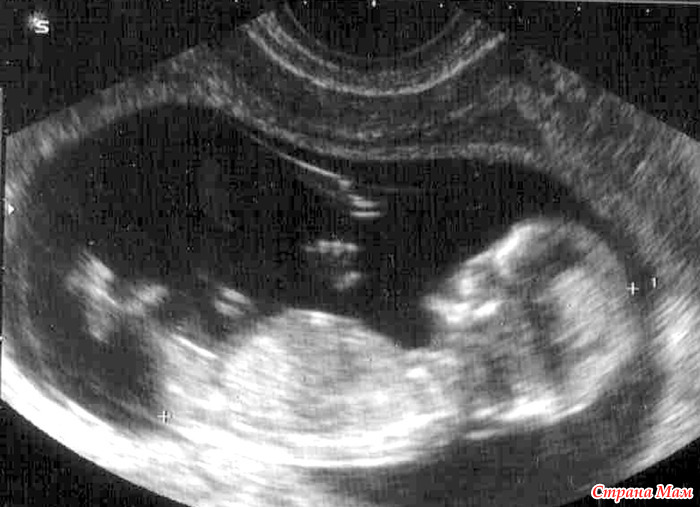

Сегодня первый раз ходила на УЗИ. Какое же это счастье видеть изображение своего будущего малыша!!! Даже не вериться, что этот маленький головастик живёт у меня в животике! Как я рада, что врач УЗИ развеял все мои страхи и переживания! От облегчения на душе, чуть не проронила слезу..... Я счастлива!